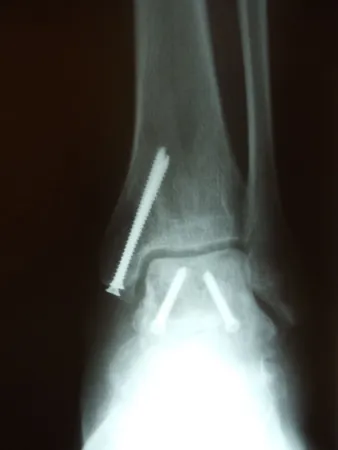

Pictures of a talar neck fracture with displacement of the talar body and subtalar and ankle dislocation prior to surgery